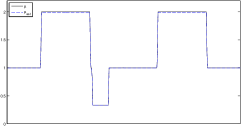

In this section, the proposed algorithm is tested on two sets of simulated two-dimensional data (with different parameter range and level of detail). We also vary the noise on the data since the reconstruction quality strongly depends on the noise level.

The data (see Figures 1 and 2) was generated in the diffusion model (1.2) using self-written (linear-basis) finite element code in MATLAB. For both examples, we took and used a uniform boundary condition . The simulated data were generated on a -grid and then down-sampled (by averaging) to to avoid inverse crime. After that, Gaussian noise with different intensities (standard deviations of and of the average signal value ) was added to the data.

Reconstruction results and error profiles at different noise levels can be seen in Figures 3 and 4. In both examples, the noise-free reconstructions are very accurate and contain mostly smoothing error. In the low-noise reconstructions, due to the fact that more regularization is necessary, some of the parameter variation is underestimated. In the high-noise examples, most detail in is lost since a lot of regularization is required to get reasonable results. The fine detail in can, however, still be recovered very accurately in both examples.